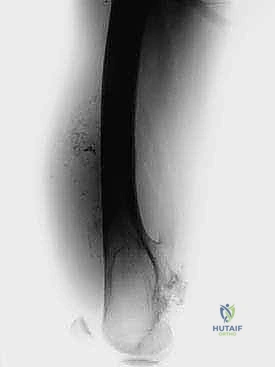

- التصوير بالرنين المغناطيسي (MRI): لتحديد الامتداد الدقيق للورم داخل العظم وفي الأنسجة الرخوة المحيطة (العضلات، الأوعية الدموية).

- التصوير المقطعي المحوسب (CT Scan): لتقييم التدمير العظمي والتخطيط للأبعاد الدقيقة للطرف الاصطناعي المطلوب.

معرض الحالات الإشعاعية: توثيق النجاح الطبي مع د. محمد هطيف

الصور الإشعاعية قبل وبعد الجراحة هي الدليل القاطع على دقة ونجاح الإجراء الطبي. نستعرض هنا مجموعة من الصور التي توضح حجم الإنجاز الطبي في استبدال العظم المصاب بمفصل معدني متطور.